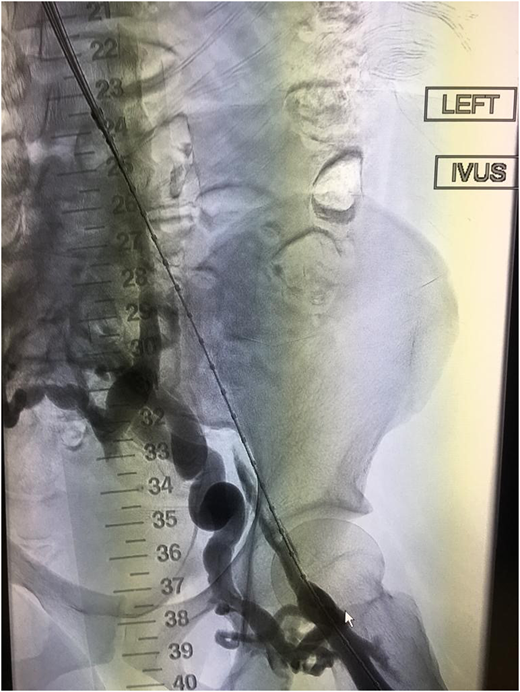

Severe PTS is often due to a chronic outflow obstruction, mainly the iliac vein, since there is usually poor collateralization of this vessel. Studies suggest when patients have severe symptoms; venous stenting is indicated when the obstruction is >50%, superficial collaterals form (Figures 2 and 3), and there is reflux in the deep and/or superficial veins.10 Femoropopliteal DVTs are best treated with anticoagulation only.

Example of thrombosed iliofemoral lesion with collateralization before venous stenting.